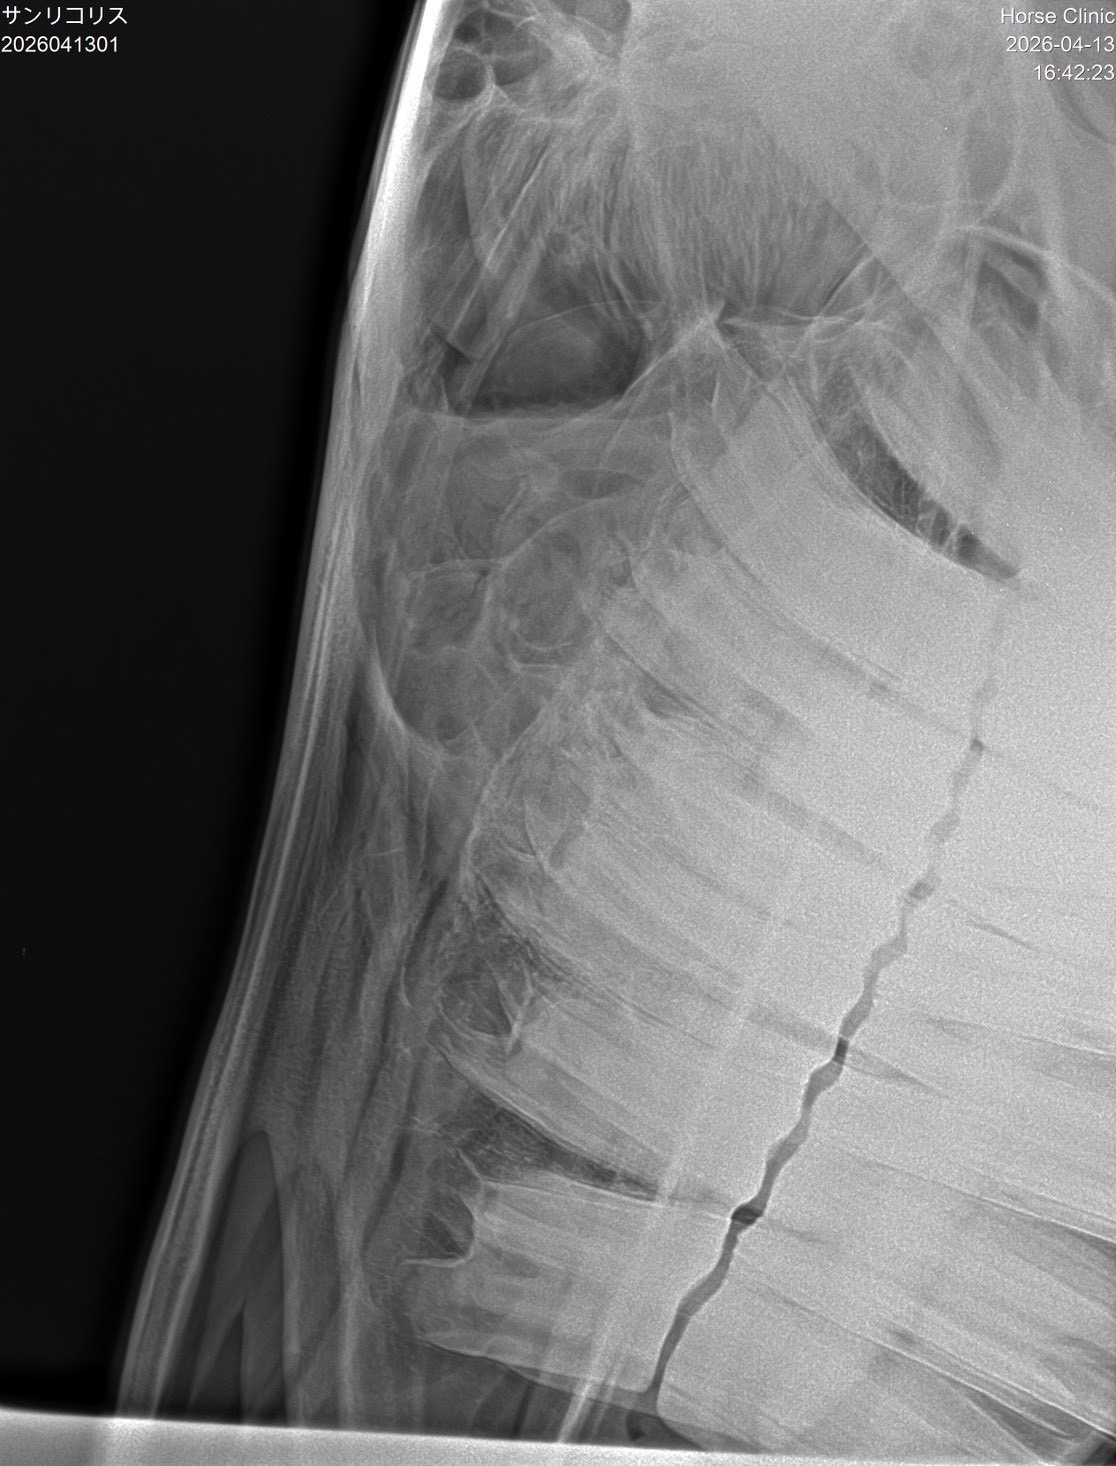

【本馬についての現状説明】

転厩当初から鼻水が止まらない状態で使っています。蓄膿症の症状で、治療は続けていますが、良くならないので、競馬でも影響が出ていると思います。頭数整理でオークション出品となりました。(川崎競馬・山崎裕也調教師)